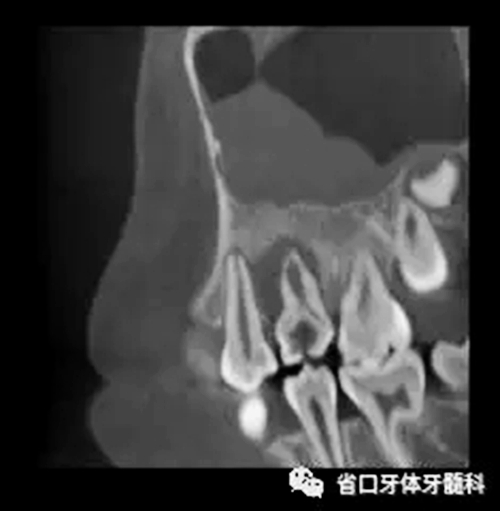

圖3 CBCT(2016-11-13):15由髓腔至根管內(nèi)見團塊阻射影像,阻射影中央為透射影,根尖1/3處見根管膨大,腭側(cè)牙槽骨破壞,根尖周低密度影范圍大,上頜竇黏膜增厚。

牙內(nèi)陷的診斷可通過口內(nèi)檢查及影像學(xué)檢查:①口內(nèi)檢查[5]: 牙形態(tài)異常,呈柱狀或桶狀、舌側(cè)有明顯凹陷,探針可探入或有嵌入感; 若牙表面無明顯凹陷,可借助龍膽紫染色來確認(rèn)有無內(nèi)陷口; ②影像學(xué)檢查: 可通過普通根尖片或CBCT,普通根尖片判斷較難,利用 CBCT 不僅可輔助診斷,還可全面地顯示根管內(nèi)的腔隙形態(tài)、牙內(nèi)陷的根管腔形態(tài)、內(nèi)陷牙的數(shù)目等指導(dǎo)治療及觀察治療后牙內(nèi)陷內(nèi)腔隙的封閉情況。

牙內(nèi)陷并發(fā)牙髓炎、根尖炎時,由于其根管結(jié)構(gòu)復(fù)雜,以往的 X 線根尖片或曲面體層攝片難以全面地顯示根管內(nèi)的腔隙形態(tài),導(dǎo)致臨床治療困難,預(yù)后較差[8]。本病例聯(lián)合使用CBCT、顯微鏡及熱牙膠技術(shù),使診斷和治療過程更加精準(zhǔn),從而保證了治療效果。